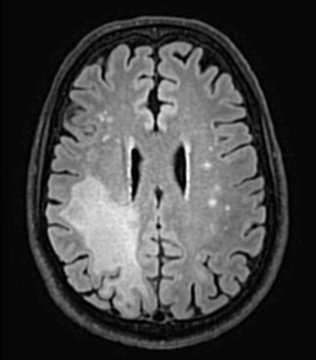

“We found both PD-1 and PD-L1 proteins in the infected parts of brains of patients with PML,” said Irene Cortese, M.D., director of the NINDS Neuroimmunology Clinic and first author of the paper. “This led us to ask whether pembrolizumab could be a potential treatment for PML.” Eight patients at the NIH Clinical Center, all of whom had signs of worsening PML, were treated with pembrolizumab. The status of their infection was monitored by MRI scans of their brains and by checking the levels of JCV in their cerebral spinal fluid (CSF). In five of the eight patients, the amount of circulating virus was reduced following treatment with pembrolizumab. Importantly, these patients’ symptoms improved or stabilized, and their brain MRIs showed shrinking of infection-related brain lesions.